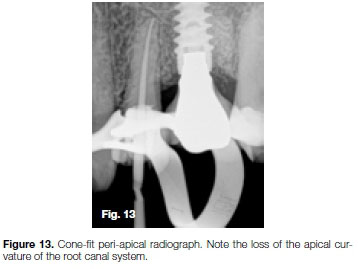

The root canal system was prepared with the Pro-Taper Universal (Dentsply Sirona) system. Incorrect use of the X3 file (30/09) resulted in apical transportation. This was visible on the peri-apical radiograph taken to confirm the cone-fit of the gutta-percha point (Figure 13). After root canal obturation it became more evident that an excessive amount of the root canal wall structure on the outside curve in the apical part of the canal was removed by the rotary file. This resulted in the loss of the original apical curvature, lack of an apical stop and subsequent extrusion of the obturation material (Figure 14).